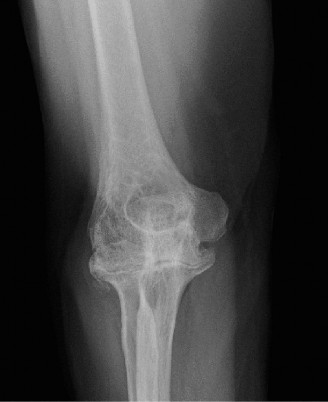

Humeral head defects >40% (Answers D, E) frequently require a large allograft or prosthetic reconstruction. If a prosthetic option is chosen, some authors recommend placing the prosthetic glenoid component in 10 to 15 degrees of retroversion for an anterior dislocation and doing the opposite for a posterior dislocation. Objectives: Did you learn...? To recognize the common presentation of a patient with a chronic dislocation? To recognize the pathoanatomic changes associated with a chronic dislocation? The various treatment options and indications for their use? CASE 17 Dr. Anna Cohen-Rosenblum A 61-year-old, right-hand-dominant female presents with 5 years of gradually worsening right shoulder pain. The pain is worse at night and she is finding it gradually more difficult to perform certain activities such as combing her hair, putting on a coat, and reaching for objects on high shelves. Past medical history includes hypertension and hyperlipidemia, both well controlled with medication. Physical examination reveals that the right shoulder appears flatter in contour compared with the contralateral side. She has diffuse tenderness to palpation about the right shoulder glenohumeral joint; range of motion of the shoulder decreased in external rotation; and 5/5 strength in the rotator cuff muscles. Imaging is shown in

Figures 2–48 and 2–49.

Figure 2–48

Figure 2–49

Based on the information and imaging, what is the most likely diagnosis?

- Osteoarthritis of the glenohumeral joint

The correct answer is (B). The patient’s chronic pain, difficulty with external rotation, flattened appearance, combined with the imaging showing narrowed joint space, subchondral sclerosis, and osteophytes at the inferior aspect of the humeral head lead to the diagnosis of glenohumeral osteoarthritis. In addition, the patient has no signs of cuff deficit on examination and no history of trauma, so Answer A is incorrect. Cuff tear arthropathy (Answer C) would also be less likely given her lack of weakness combined with imaging showing typical signs of osteoarthritis without a high-riding humeral head as would be characteristic of a massive cuff tear with resulting arthropathy. Finally, Answer D is incorrect because, even though it is probable a person her age would have a labral tear, it would manifest more as mechanical symptoms and/or instability.